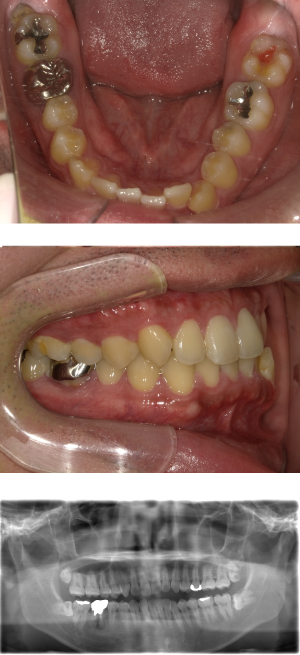

インプラント治療(左上5ソケット・GBR 右上2左上13GBR)

| 年代・性別 | 50代・男性 |

| 主訴 | 入れ歯だと咬めなくてつらい。 |

| 部位 | 上顎②1①2③4⑤Br |

| 治療期間 | 約9ヶ月 |

| 費用 | ¥1,794,100(税込) |

| 副作用・リスク |

|